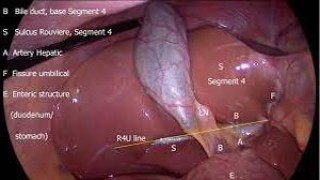

Incisional hernias, especially large or massive ones, pose significant challenges in surgical management due to the risk of complications, adhesions, and recurrence. With advancements in minimally invasive surgery, laparoscopic repair has become the preferred approach for complex hernias, offering numerous advantages over traditional open surgery. Dr. R.K. Mishra, a pioneer in laparoscopic surgery, has successfully performed laparoscopic repairs for huge incisional hernias, demonstrating exceptional surgical precision and patient outcomes. Procedure Overview: Laparoscopic repair of a huge incisional hernia involves small keyhole incisions through which specialized instruments and a high-definition camera are inserted. The hernia sac and its contents are carefully reduced, and adhesions are meticulously released to create a safe working space. A large surgical mesh is then placed over the defect and securely fixed, ensuring strong reinforcement of the abdominal wall while minimizing tension. Advantages of Laparoscopic Approach: Minimally Invasive: Small incisions reduce postoperative pain, scarring, and infection risk. Faster Recovery: Patients often resume normal activities sooner compared to open surgery. Reduced Complications: Lower risk of wound infections and seromas. Precision and Visualization: Enhanced laparoscopic imaging allows careful dissection even in complex, large hernias. Durable Results: Properly placed mesh ensures long-term strength and reduces recurrence rates. Dr. R.K. Mishra’s Expertise: With decades of experience in advanced laparoscopic and robotic surgery, Dr. Mishra brings unparalleled skill in managing giant incisional hernias. His approach emphasizes meticulous technique, patient safety, and individualized surgical planning. By combining the latest minimally invasive techniques with his surgical expertise, Dr. Mishra has transformed outcomes for patients with challenging abdominal wall defects. Patient Outcomes: Patients undergoing laparoscopic repair under Dr. Mishra’s care experience shorter hospital stays, minimal postoperative discomfort, and quicker return to daily activities. The success of these procedures has positioned World Laparoscopy Hospital as a leading center for advanced hernia management globally. In conclusion, laparoscopic repair of huge incisional hernias by Dr. R.K. Mishra represents a significant advancement in hernia surgery, offering patients safer, faster, and more effective treatment options compared to traditional methods.